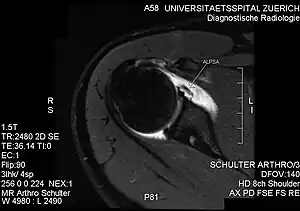

| PD-weighted MRI with fat saturation of the shoulder showing an ALPSA lesion | |

An ALPSA (anterior labral periosteal sleeve avulsion) lesion is an injury at the front of the shoulder associated with shoulder dislocation.[1]

The anterior (front) labrum can peel off the glenoid resulting in a Bankart lesion. When the periosteum (fibrous tissue surrounding bone) peels off as well this is called an ALPSA lesion. When this happens the labrum (bumper) falls away and rolls up. It normally falls medially and downwards.

The evaluation of ALPSA lesions are done via magnetic resonance angiography and arthroscopy[2]